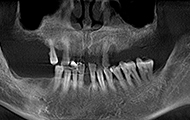

缺了8颗牙,名副其实的“缺牙一颗带坏全口”,在检查后,我右边的第一缺牙已经有严重的骨萎缩了,是“纸片骨”,种牙难度很大,我从湖南跑到深圳,可以说一路都在对比医院和方案。

我听过的拒诊理由很多,有“年纪太大了,怕风险高”,“你这骨量不好,种牙难度太大了”,“缺牙数太多,难度也大,可以做但是很贵,你还是换其他方法吧”,在这里我看到了希望…医生技术好,还会为我省钱,给过做种植体+冠桥,缺了8颗大牙,种6颗种植体就够了。

面对我参差不齐的骨量,整个团队都围绕着我想方案,最终确定了给我骨粉骨膜搭配植骨的方式重新夯实我的骨量,老爷子我很感恩。